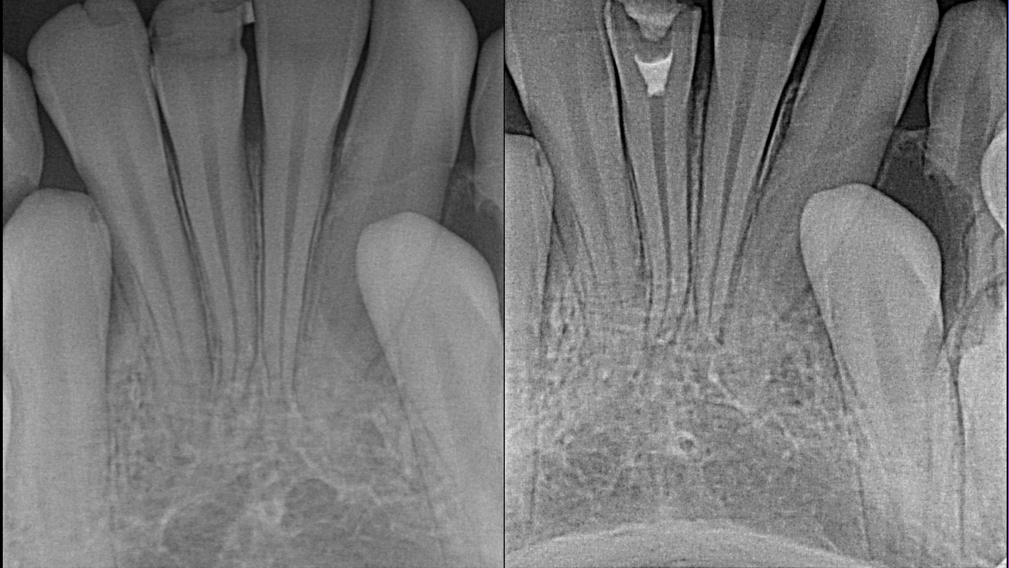

Damas-Case-1a-thumbnail alternate text for this image

Endodontic therapy involves treating infected pulps to save a tooth that otherwise may need to be removed. This treatment can become significantly more challenging when dealing with the adolescent dentition and underdeveloped teeth. The primary goal as clinicians is to restore function to the dentition. In the adult fully developed dentition, when extraction is the … Read more